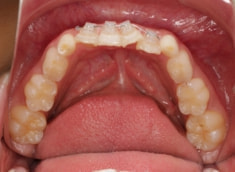

治療前